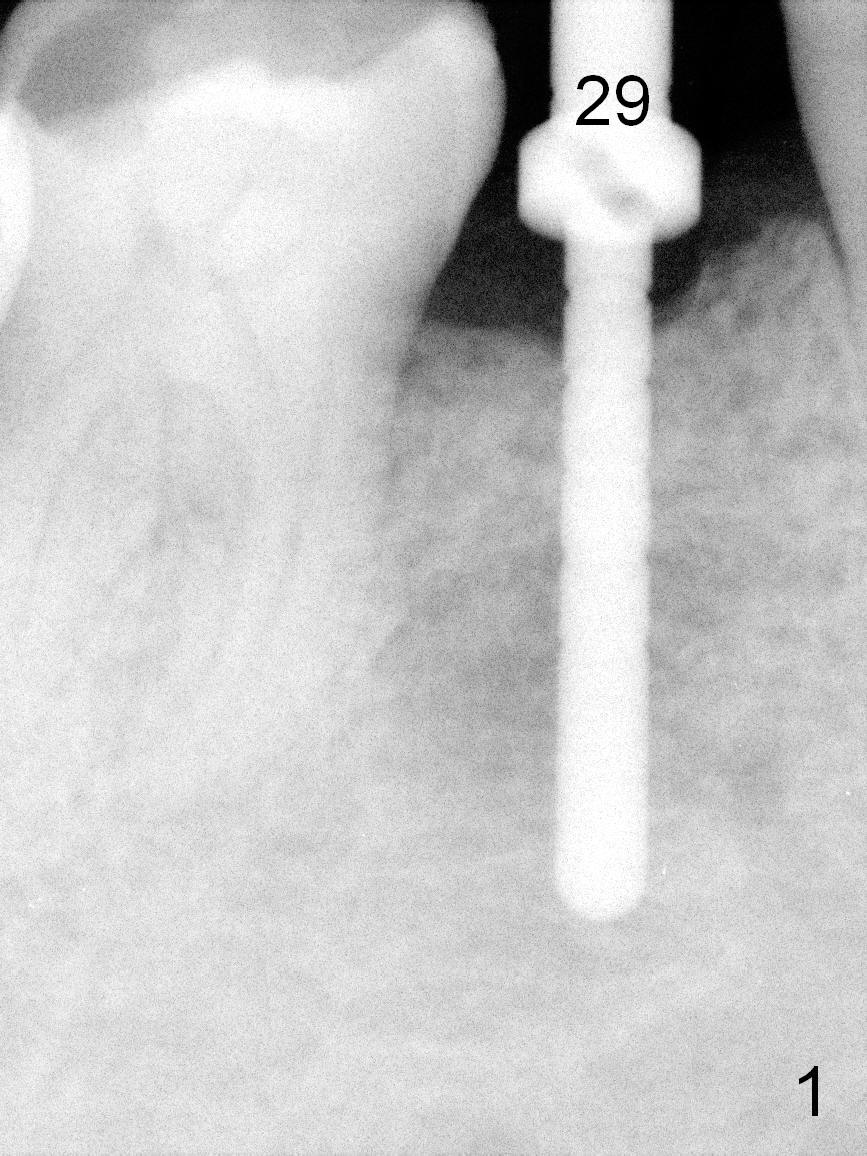

Partial edentulism with or without partial denture (especially in males) is more likely associated with implant failure than full dentition. Mr. Wang has lost several teeth (including #29, Fig.1) with secondary malocclusion, particularly supraeruption of the tooth #4. When a 3.8x10 mm submerged implant is placed with insertion torque >35 Ncm (Fig.2), an immediate provisional is selectively not placed to avoid micromovement. Instead, a healing abutment (5.2x5(3 mm) is placed immediately. For wound protection, periodontal glue and periodontal dressing are supplemented after suturing. Due to severe supraeruption of the tooth #4, the patient feels mild pain when he bites down heavily, a few hours postop. It is possible that the supraerupted tooth touches the periodontal dressing. The implant appears to be osteointegrated 4 months postop (Fig.3). A provisional is fabricated after placement of a cemented abutment (4.8x5(3) mm) to intrude the opposing tooth. There is no bone loss 2.5 years post cementation (Fig.4 CT).